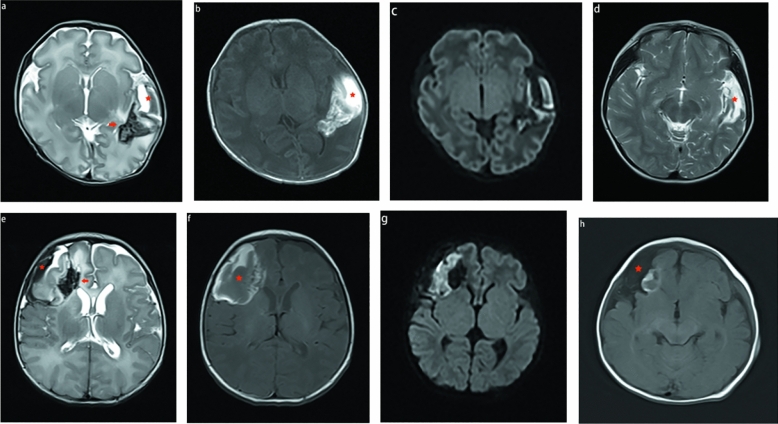

The third pattern was observed in 23 patients. On T1WI, T2WI, and DWI, the signals of the subpial hemorrhage and subjacent parenchymal hemorrhage were complex and variable because of the different bleeding times. The subpial collection demonstrated both hyperintensity and hypointensity on T1WI and T2WI, but only two patients showed restricted diffusion. Ten of the 23 MRI scans showed fluid–fluid levels. The main manifestations of parenchymal hemorrhage on T1WI, T2WI, and DWI were heterogeneous signals, and the involved cortex was predominantly hyperintense on T2WI and restricted diffusion imaging (Figs. 3 and 4). In this pattern, the signal of the subpial hemorrhage was completely different from that of the adjacent parenchymal hemorrhage on T2WI, so the subpial hemorrhage, underlying cerebral cortex, and adjacent white matter hemorrhage created the yin-yang sign or sandwich sign. If the involved cortex and white matter signal changes were consistent without a dark, thin fluid layer, they were visible as a yin-yang sign (n = 3) (Fig. 3); otherwise, they presented as a sandwich sign (n = 20) (Fig. 4).

Figure 3.

MR image of a full-term neonates with pattern C. The subpial hemorrhage shows hypointense on T2WI and hyperintense on T1WI. Hemorrhage is seen in the underlying cerebral cortex and white matter, resulting in a hyperintense on T1WI and T2WI (a-b). There was no restricted diffusion in the subpial bleed and hyperintense on underlying cerebral cortex and white matter (c). SWI shows magnetic susceptibility artifact blurs, making it diffcult to separate the subpial hemorrhage from underlying the cortical ribbon ( d, arrowhead). This combination of a dark subpial hemorrhage collection and the bright underlying cerebral cortex and white matter forms a yin-yang sign (a and c).

Figure 4.

MR images of 2 neonates. The first patient (a–d) is a preterm neonate, and the second patient (e–h) is a term neonate. The first MRI shows (a–c and e–g) a subpial bleed (star), underlying the cerebral cortex and white matter with fan-shaped hemorrhage (arrow) created a sandwich sign. We found the medullary veins were notably enlarged (arrow in a and e). Reexamination after 3 years (d) and 5 months (h) showed that the subpleural hemorrhage and cerebral parenchymal hemorrhage had been absorbed and eventually encephalomalacia and gliosis. Subpial cystic cavities were formed (red star in d and h).